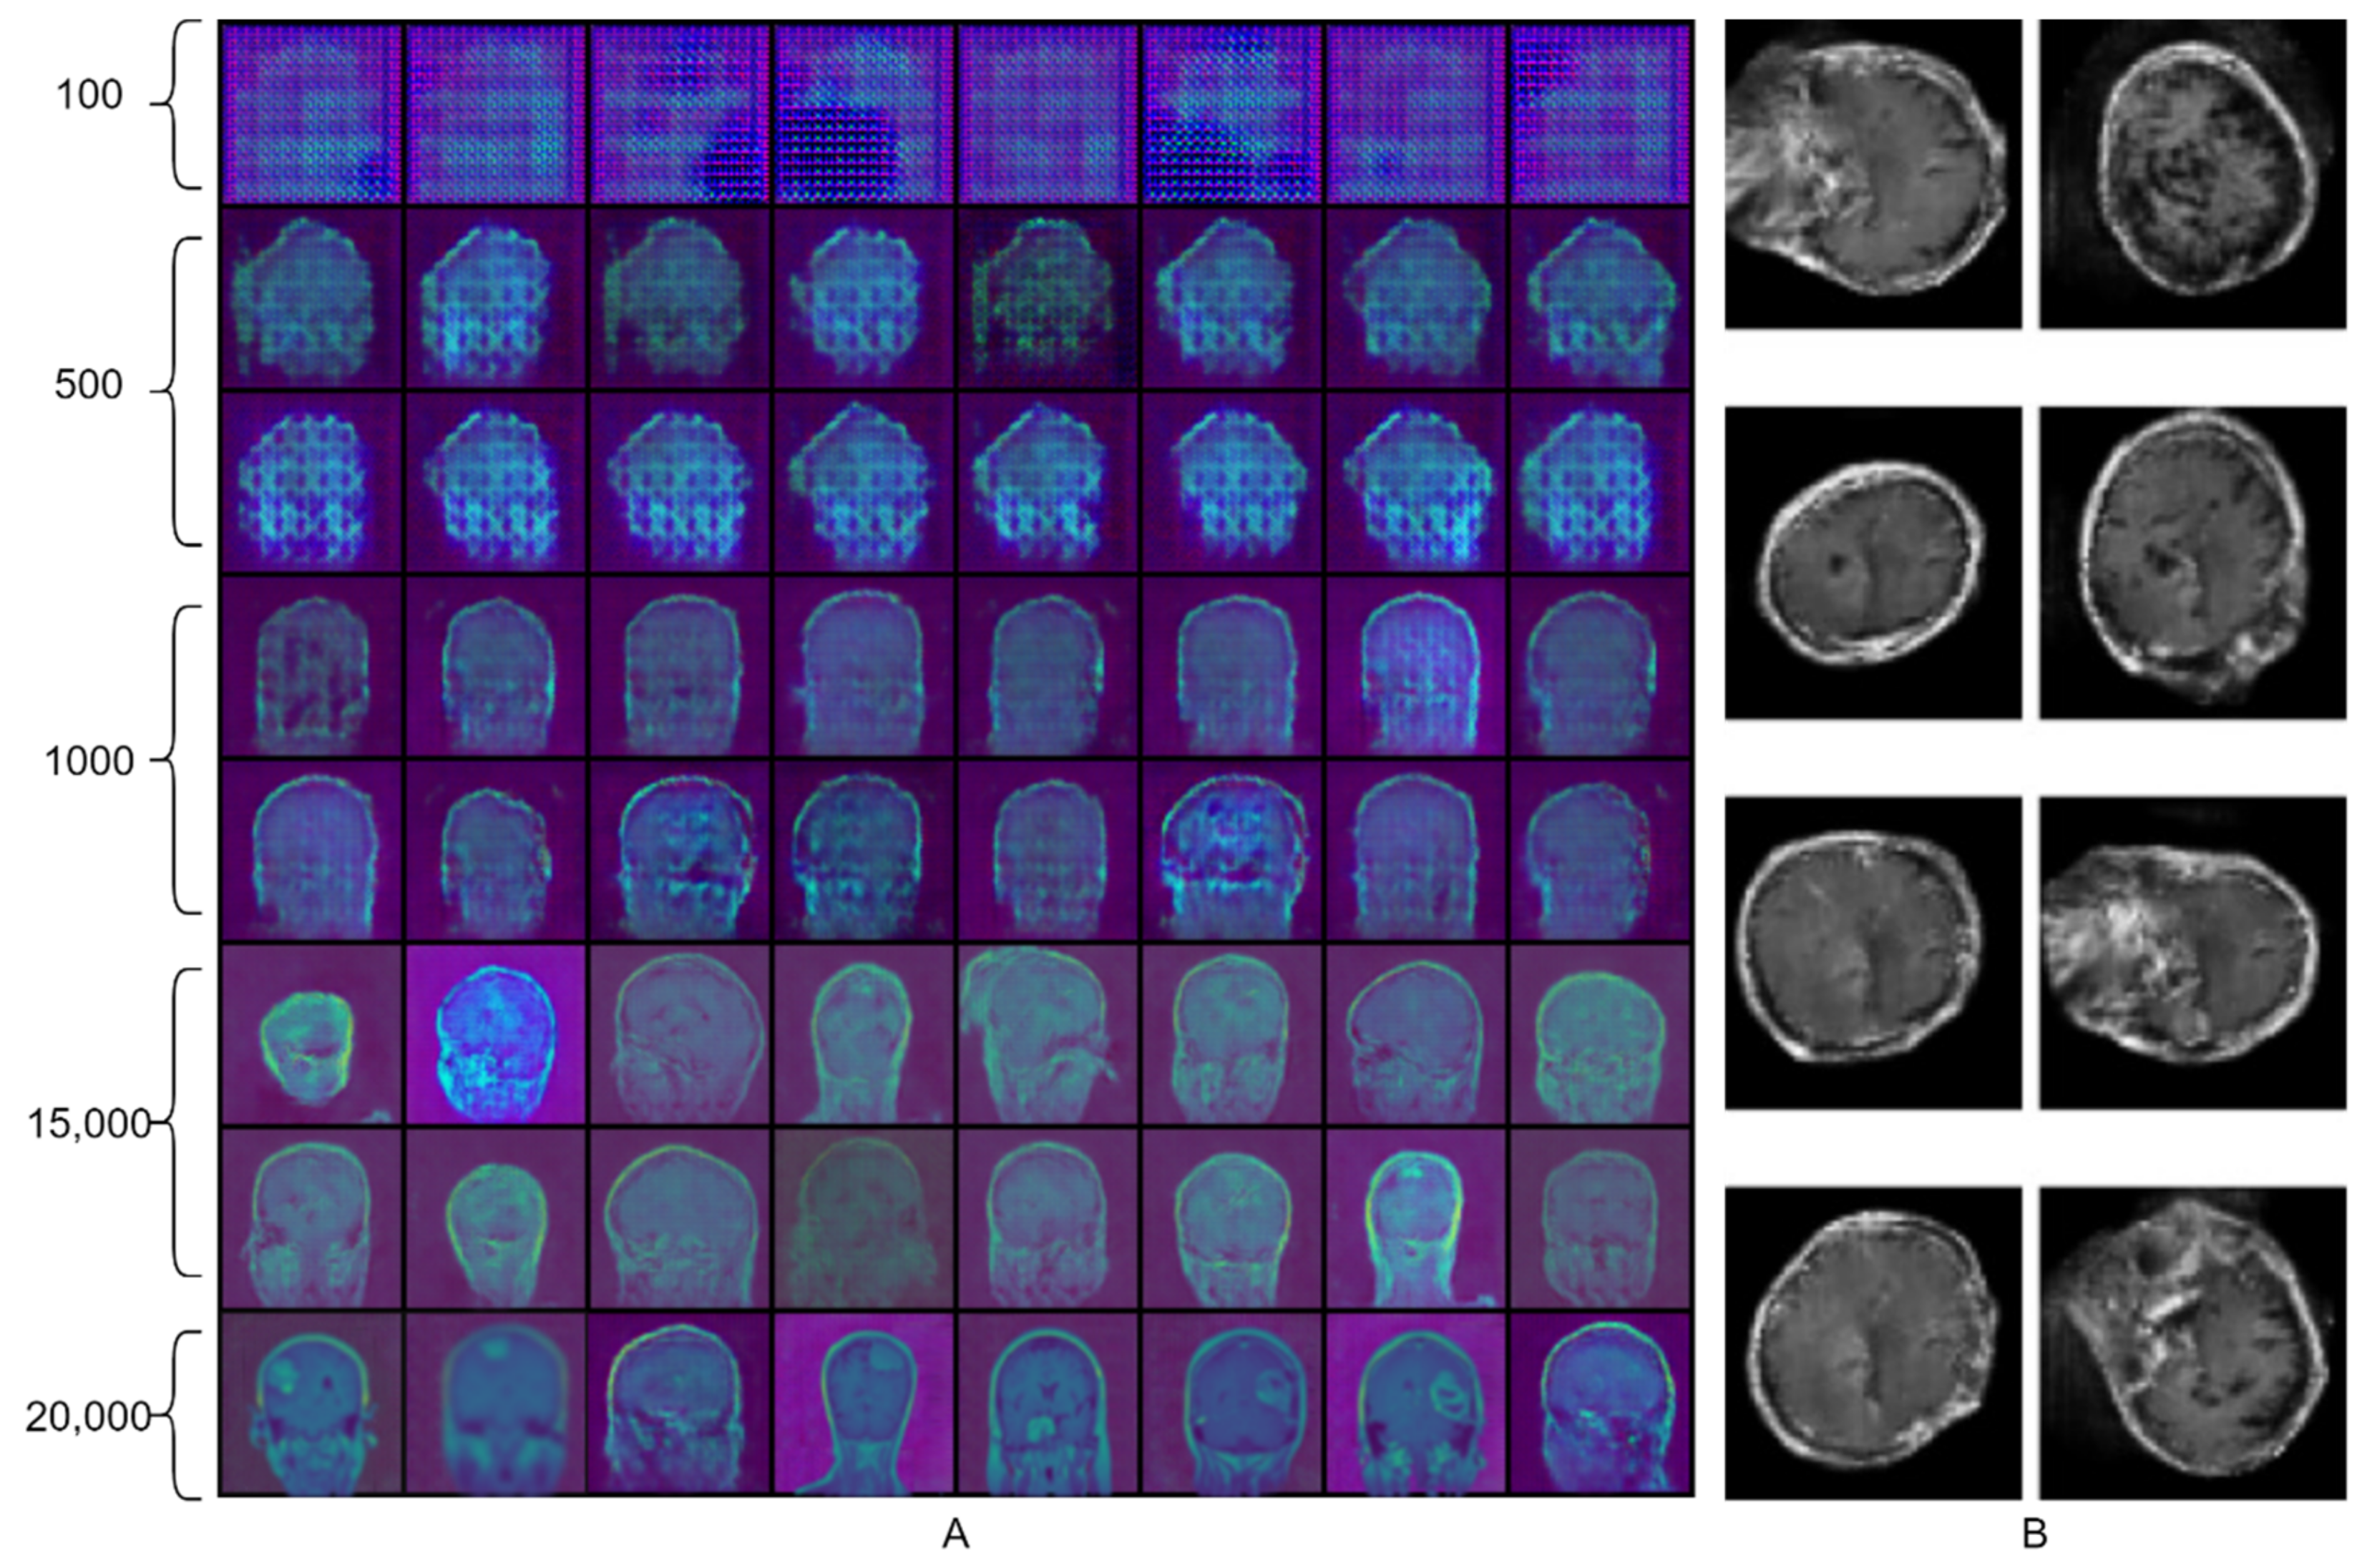

With all the wonderful progress of medicine over the last decades, some diseases are still life-threatening and, among them, brain cancer is the most aggressive [1]. Uncontrolled irregular growth of protein inside and around the brain tissues is known as a brain tumor. A brain tumor can be malignant or benign, malignant being the most aggressive type. In layman’s terms, the malignant type of brain tumor is called brain cancer. If a tumor breaches the covering and spreads into other parts, it is considered cancer [2]. Pituitary, meningioma, and glioma tumors are the three basic categories of brain tumors. The pituitary is a gland located at the base of the brain, and any abnormal growth of protein around this gland is known as a pituitary brain tumor [3]. Meningioma is a benign tumor that develops slowly and is found on the brain’s outer coverings beneath the skull [3]. The last and most aggressive one is glioma, with the highest mortality rate worldwide among all brain tumors [4]. It is commonly found in the cerebral hemispheres and the supporting tissue cells of the brain. Because of the location of the various brain tumors, pituitary and meningioma tumors are easy to detect, but gliomas are difficult to detect and analyze [3]. Sample images of glioma, meningioma, and pituitary from the dataset used in this research are presented in Figure 1.

In this study, we used the public dataset proposed by Cheng [47]. It contains 3064 CE-MR images of three types of brain tumor (glioma, pituitary, and meningioma) from 233 patients. The images in this dataset are two-dimensional (2D-slices), not 3D volume images. This study included all three planes (axial, coronal, and sagittal) images from this dataset. A few sample images are depicted in Figure 1. Further details about the dataset and the training-test split are presented in Table 2.

Figure 1. Sample images from the dataset. The first, second, and third rows of images represent glioma, meningioma, and pituitary brain tumors.